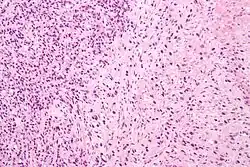

Gleason 3

Gleason 3 is a clearly infiltrative neoplasm, with extension into adjacent healthy prostate tissue. The glands alternate in size and shape, and are often long/angular. They are usually small/micro-glandular in comparison to Gleason 1 or 2 grades. However, some may be medium to large in size. The small glands of Gleason 3, in comparison to the small and poorly defined glands of pattern 4, are distinct glandular units. Mentally you could draw a circle around each of the glandular units in Gleason 3.[4][7]

Gleason 4

Gleason pattern 4 glands are no longer single/separated glands like those seen in patterns 1–3. They look fused together, difficult to distinguish, with rare lumen formation vs Gleason 1–3 which usually all have open lumens (spaces) within the glands, or can be cribriform-(resembling the cribriform plate/similar to a sieve: an item with many perforations). Fused glands are chains, nests, or groups of glands that are no longer entirely separated by stroma-(connective tissue that normally separates individual glands in this case). Fused glands contain occasional stroma giving the appearance of "partial" separation of the glands. Due to this partial separation, fused glands sometimes have a scalloped (think looking at a slice of bread with bite taken out of it) appearance at their edges.[4][7]